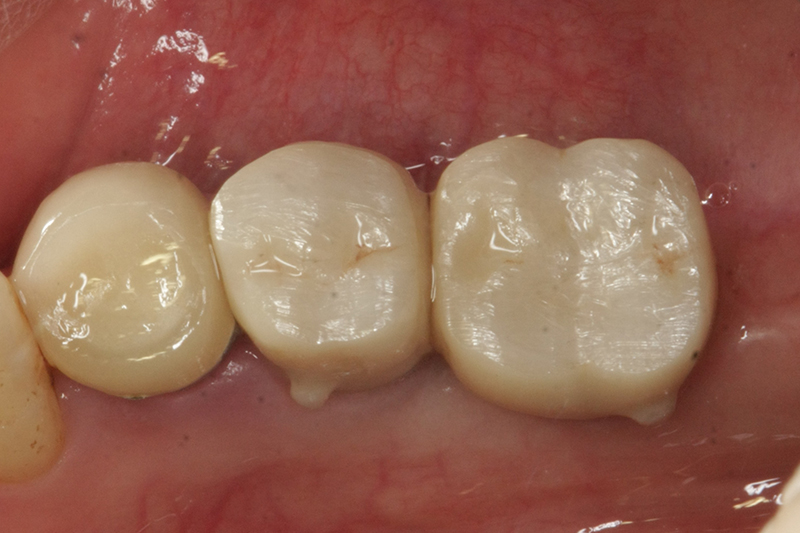

缺牙多顆

案例二

術前

術中

術後